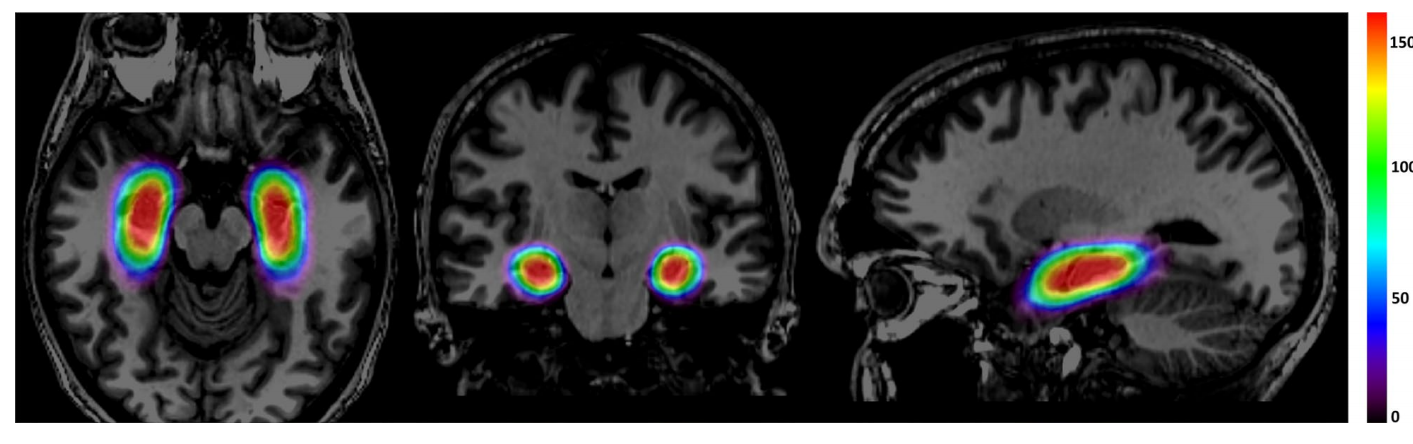

11个综合癫痫中心175例患者消融分布的热图。全部消融(红色)均以AHC长轴为中心,并向后延伸至外侧中脑沟水平。消融位置的变化表现为较不频繁消融的区域(绿色和蓝色)从这个中心延伸出来